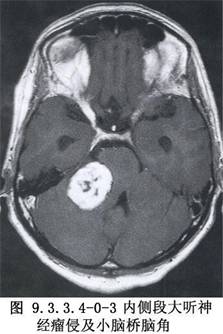

聽神經瘤是指生長在蝸神經及前庭神經各分支上的神經鞘膜瘤,70%以上原發於前庭神經,其中以前庭上神經爲多。是由胚原性Schwann細胞異常增生而成,可發生在神經乾的任何部位。最常發生於位靠內耳道底的神經鞘膜Schwann細胞與神經膠質細胞銜接的節點上。聽神經瘤組織學屬良性病變,生長緩慢。臨牀確診者半數以上在30~50歲之間,女性多於男性,多爲單側性。其臨牀發病率各家統計不一,約爲0.1‰~0.2‰,居顱內腫瘤的第3位,佔腦橋小腦三角腫瘤的70%以上。顳骨病理學家們早就指出,隱性聽神經瘤的發現率很高。Hardy(1936)在顳骨切片中發現聽神經瘤佔2.%(6/250);Schuknecht(1975)統計佔0.97%(5/517),姜泗長(1987)統計爲0.43%(1/231),均爲臨牀聽神經瘤確診率的數十倍之多,足見聽神經瘤漏診率之高。隨着人們對聽神經瘤認識的加深及耳神經學、影像診斷學的發展,會有更多病人獲得早期診斷,而不至等到顳骨切片時才發現。因此,早期診斷和治療聽神經瘤應視爲耳科醫師們的神聖職責之一(圖9.3.3.4-0-1~9.3.3.4-0-3)。